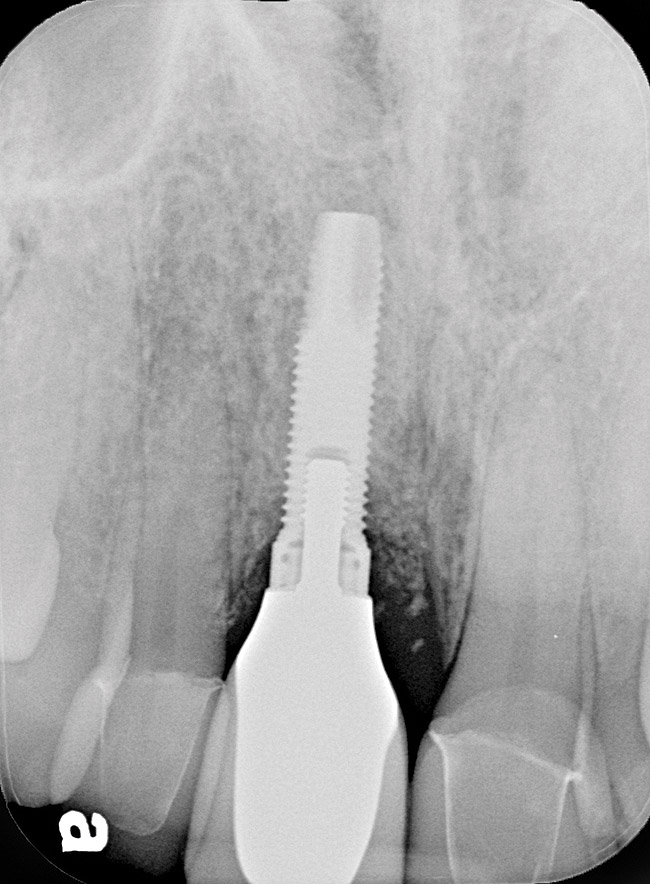

Figure 7  Radiograph depicting loss of supporting bone around the implant.

Figure 7

A 46-year-old man with an unremarkable medical history was referred for evaluation and treatment of the maxillary right central incisor implant. The implant, which had been placed 6 years prior, had never caused any problems until recently, when the patient noted both swelling and soreness at the site. Following 10 days of amoxicillin 500 mg tid, purulence was still present upon palpation of the tissue, and the patient was referred for consultation (Figure 6). Probing attachment loss of 10 mm on the distal aspect and 5 mm on the mesial were measured around the implant. Bone loss was advanced on the periapical radiograph at both the mesial and distal aspects of the hydroxyapatite-coated implant (Figure 7). Full-thickness facial and lingual flaps were reflected to access the implant and surrounding bone, with care taken to preserve the papilla. The defects around the implant on the mesial and distal were 1-wall, and bone loss was present on the direct facial and palatal aspects as well (Figure 8). The surface of the implant was decontaminated, followed by application of enamel matrix derivative. The lesion was filled with freeze-dried bone allograft (Figure 9). The graft-biologic was covered by a flowable polymer barrier (Figure 10). The flaps were coronally advanced and secured with monofilament sutures (Figure 11). The patient was prescribed amoxicillin with clavulanic acid and an oral rinse of 0.12% chlorhexidine during the post-operative period. The healing progressed uneventfully, achieving both a favorable soft-tissue profile and substantial bone fill, as determined radiographically. These results were stable for 7 years (Figure 12 and Figure 13).